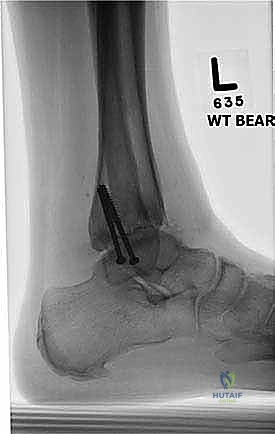

- الأشعة السينية أثناء الوقوف (Weight-bearing X-rays): هي الفحص الذهبي والأهم. يجب أن تؤخذ الأشعة والمريض واقف لتحمل الوزن. تظهر الأشعة تضيق المسافة المفصلية (دليل على فقدان الغضروف)، وجود نتوءات عظمية، تصلب العظم، وأي انحراف في محور المفصل.

- التصوير المقطعي المحوسب (CT Scan): يطلبه الدكتور هطيف لتقييم جودة العظام (Bone stock)، تحديد حجم الأكياس العظمية، ورسم خريطة ثلاثية الأبعاد للتشوهات المعقدة قبل الجراحة.

- التخطيط الجراحي الرقمي: باستخدام صور الأشعة المقطعية، يقوم الدكتور هطيف بتخطيط الجراحة على الكمبيوتر لاختيار حجم المسامير والشرائح المناسبة بدقة مليمترية.